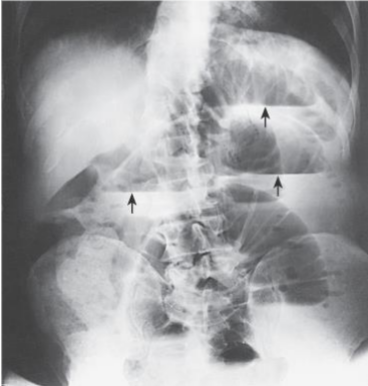

Ascites in the build up of ____ in the space between the lining of the abdomen and abdominal organs

fluid

Ascites commonly occurs due to what type of disorders

liver